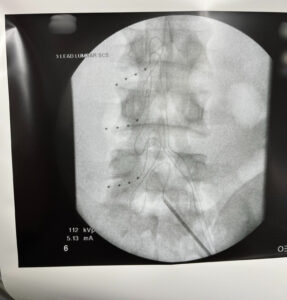

Dr. Suneil Jolly, Medical Director of Louisiana Pain Specialists, recently completed a highly complex dorsal root ganglion procedure. With the help of the ProclaimTM DRG System from Abbott, this procedure is expected to produce a complete quality of life upgrade for the receiving patient.

The receiving patient had suffered from chronic nerve pain after a crush injury. The use of the DRG implant provides targeted pain relief to the area producing an improved quality of life. This procedure has also enabled the patient to avoid costly back surgery while returning them to a more normal function of their everyday life.